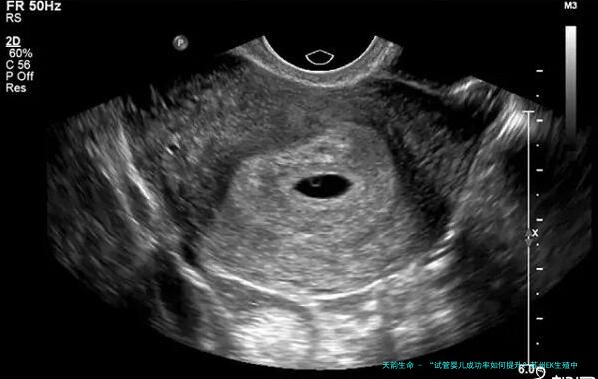

胎心监护是利用超声波对胎儿的情况进行监测,是临床上正确评估胎儿宫内的状况的主要检测手段,孕妇进行胎心监测有利于判断胎儿有无出现缺氧情况,如果在进行检查的过程中胎儿心跳过于频繁或胎心率较慢,可以在医生的指导下采取适当措施。虽然临床上胎心监护没有具体的检查时间,但大致来说,孕妇进行胎心监测检查的时间可以以下这点进行安排: